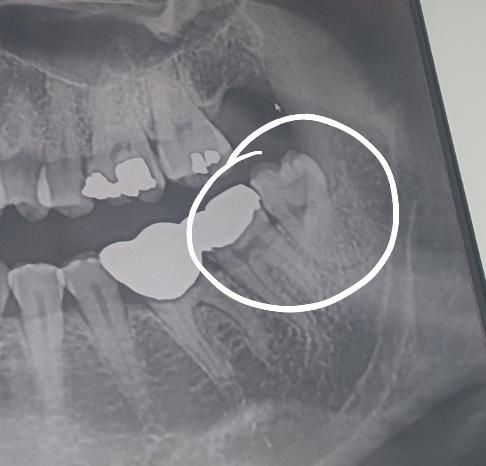

치과상담 받아보니 뿌리가 아주 약간휘어져있다곤 하시는데요

매복치는 아니고 이건무슨 사랑니인가요? 부분매복인가요?

왼쪽 하악입니다..

그리고 신경하고 많이 가까운편인가요? 전달마취 라는 건 꼭 해야 하는거죠?...

• 1번 째 사진

3. 매복아니고 정상맹출 사랑니입니다

4. 신경관이랑 거리 충분해보입니다